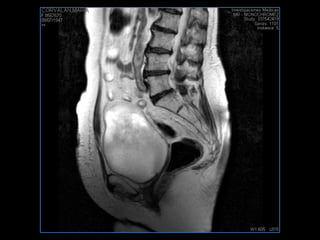

PROTOCOLO pelvis SAG T2, Y FAT SAT (FINOS) AXIAL T1  AX FAT SAT CON   GADOLINIO :  AX T1 Y COR T1 SAT: NO  FASE: RL THK: 3MM  COIL:  GAP: (FACTOR 1.4) 1MM FOV: 40 CM NEX:2 SINCRONIZACION RESPIRATORIA EN 3 O 4 CICLOS ALE